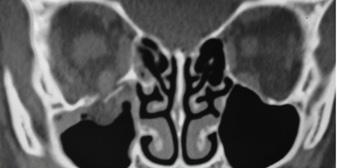

Celulitis orbitaria (Postseptal)

DEFINICIÓN

Una infección del contenido orbitario, como la grasa y los músculos extraoculares.

Posterior al tabique orbitario

ETIOLOGÍA

Complicación de la infección del tracto respiratorio superior, más comúnmente debido a rinosinusitis bacteriana (Niños: sinusitis etmoidal)

DIAGNÓSTICO

Además de los que se presentan en la celulitis periorbitaria

Proptosis (protrusión hacia adelante del globo ocular)

Oftalmoplejía (el dolor es más severo y restringe los movimientos)

↓ agudeza visual

TRATAMIENTO

El tratamiento antibiótico intravenoso empírico incluye vancomicina + uno de los siguientes: ceftriaxona, cefotaxima, ampicilina-sulbactam, piperacilina-tazobactam. El drenaje quirúrgico está indicado en la formación de abscesos.

COMPLICACIONES

Absceso subperióstico, orbitario o cerebral Trombosis del seno cavernoso (ENAM 2011): cefalea, parálisis de pares craneales (III, IV, V1, V2 y / o VI), edema periorbitario y proptosis de forma bilateral.

Figura 15. Celulitis orbitaria se complica con trombosis del seno cavernoso (ENAM 2011)